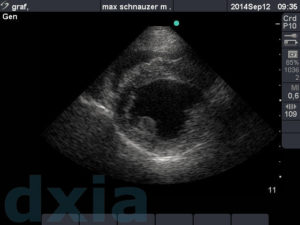

Imágenes obtenidas durante el estudio ecocardiográfico

paraesternal max

Paraesternal derecho eje largo

No se observa dilatación de cámaras cardíacas. Septo IV normal. Válvulas mitrálica y tricuspídea normoimplantadas y sin alteraciones morfológicas.